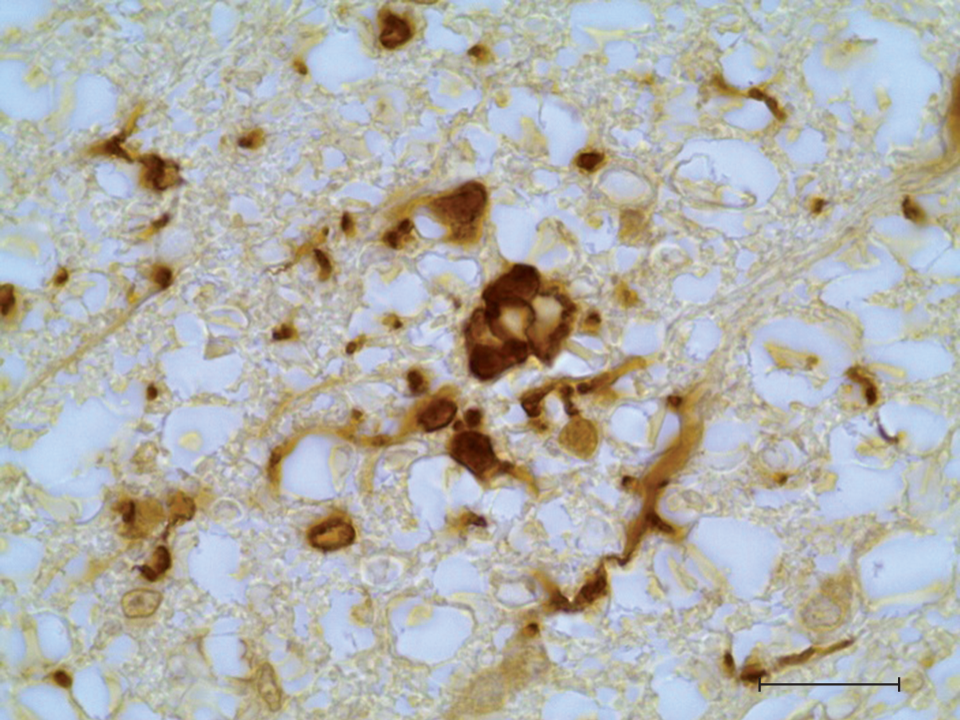

It is widely known that neuroinflammation is a key factor in the development of many neurological pathologies and neurodegenerative diseases. The dynamics of development and duration of neuroinflammatory responses are critical aspects in understanding the patterns of physiological, biochemical and behavioral consequences. The most common object of study is neuroinflammation that develops after experimental systemic inflammation. The effect of acute systemic inflammation on brain microgliocytes has been studied extensively, while spinal cord microglia have been studied less frequently. The purpose of this study was to assess the topographic and temporal features of morphofunctional changes in rat spinal cord microglial cells after experimental LPS-induced systemic inflammation. It has been established that in the early stages of neuroinflammation (24 hours after LPS administration), microgliocytes are activated in the ventral white and ventral gray matter of the spinal cord. At the same time, microgliocytes of the dorsal part of the spinal cord do not show morphological attribute of activation. An increase in the population density of microgliocytes in the ventral funiculus of the spinal cord was noted. Accumulations (aggregates) of reactive microgliocytes were also found in this area.